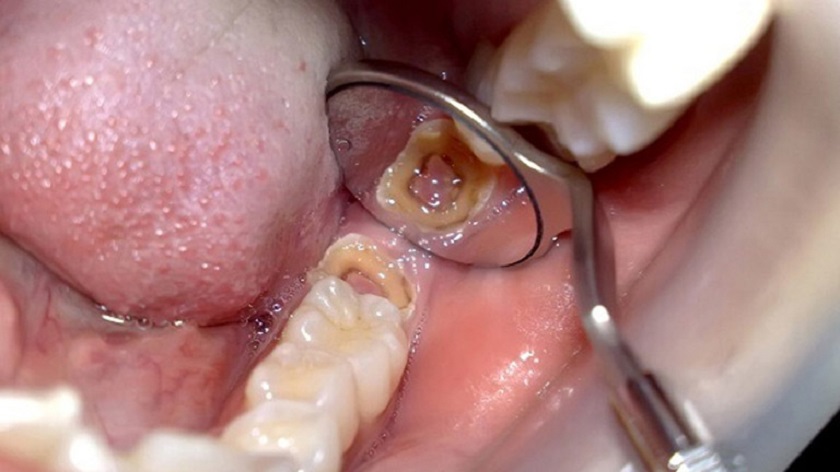

Tình trạng răng khôn bị sâu

Răng khôn thường mọc tại vị trí trong cùng trên khuôn hàm, do nằm sâu bên trong như vậy nên việc vệ sinh hàng ngày tương đối khó khăn. Cũng vì thế mà nguy cơ sâu răng khôn khá cao. Cùng với đó, nướu tại khu vực này cũng dễ bị viêm nhiễm, sưng tấy làm bạn cảm thấy khó chịu và phiền toái vô cùng.

Phần nướu bị răng khôn làm tách ra còn làm cho thức ăn dễ kẹt lại. Trong khi đó, việc vệ sinh khu vực này rất khó vì răng khôn mọc ở góc hàm trong cùng. Điều này tạo cho vi khuẩn điều kiện phát triển thuận lợi, gây sưng đau và viêm nhiễm. Ngoài ra, quá trình phân hủy protein của vi khuẩn sẽ gây mùi hôi khó chịu, đây cũng là nguyên nhân vì sao nhiều người bị hôi miệng khi mọc răng khôn.